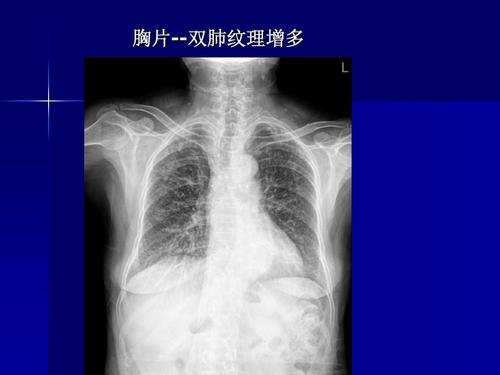

肺部图片胸片,胸片图片肺大泡

影像解剖入门正常胸片怎么看

x线胸片阅读基础ppt

(经验)实习生如何读胸片

胸片图片

正常胸片图片图解

正常胸片和肺炎胸片图

正常肺部胸片

正常胸片影像图片